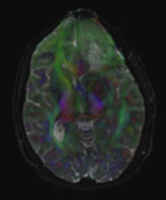

• focusing on DTI only: issues

• T1 is too high resolution to resample DTI into (will cause memory problems); use subsampled version T1_sub instead.

• initial misalignment is regional only, BSpline portion is sufficient (no affine required)

• masking is required for successful registration: BRAINSfit requires two masks: moving mask for the DTI_base we get from the initial DTI_estimation; for the fixed mask T1_sub we use the same one but resampled (T1_sub_mask).

• BRAINSfit registration will take ca. 90seconds with default settings and parameters as suggested below

• BRAINSfit parameters: fixed volume: T1_sub, moving volume: DTI_base; check: "include BSpline Registration Phase"; output: Slicer BSpline Transform : create new; output image volume: create new; output image pixel type: short; Registration parameters: number of grid subsdivisions; = 7,5,5 ; Control of mask processing: check ROI; input fixed mask = T1_sub_mask; input moving mask: DTI_maskj

• DTI resampling is done via ResampleDTI Volume module. Parameters

• Input Volume: DTI, Output Volume: create new; Reference Volume: "T2-sub"; Transform Node: Bspline Xform produced by BRAINSfit, check output-to-input" box.

• DTI processing (Alex Yarmarkovich, Demian Wasserman)